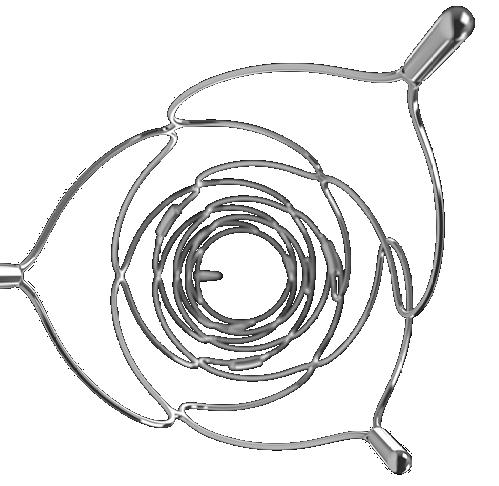

In light of a recent publication detailing the safe and effective use of the Solitaire X 3mm (Medtronic) stent retriever in medium- and distal-vessel occlusion (MeVO/DVO) stroke, Marios Psychogios (University Hospital Basel, Basel, Switzerland) discusses the relevance of having a dedicated device for these cases, as well as providing insight on what he feels is the “next frontier” in mechanical thrombectomy.

“We were one of the first clinics that used the device in Europe, and we are happy with it,” Psychogios says, highlighting navigability and radial force as being among key characteristics of the Solitaire X 3mm. “Generally, I like these aspects—the navigability for those superiortrunk M2 and M3 occlusions is really good, and it still has enough radial force to actually be able to capture clots [in those locations].”

He attributes these abilities, at least in part, to the device’s parametric design, which helps it to better accommodate the clot while also providing a strong balance of navigability and radial force, as well as the right level of retrievability and “softness” for use in more distal vessels.

“What [Medtronic] has done nicely here is find the ‘sweet spot’ of combining all these things,” Psychogios adds.

Writing in the Journal of Clinical Medicine, Psychogios et al recently published findings from a retrospective study involving 68 consecutive primary and secondary MeVO/DVO stroke cases treated via thrombectomy across 12 European centres.1 Psychogios is keen to emphasise “really good” reperfusion results reported in the paper—as per the study’s primary endpoint, the Solitaire X 3mm achieved a first-pass rate of complete or nearcomplete reperfusion (modified treatment in cerebral infarction [mTICI] 2c–3) of 32.3%.

Other key statistics he highlights are a final-pass mTICI 2c–3 rate of 67.6%, a final mTICI 2b–3 rate close to 90%, and—regarding safety endpoints—a 13% rate of intracranial haemorrhage (ICH), with none of these complications being symptomatic or resulting in subsequent neurological deterioration. The researchers also observed no device malfunctions in the study. Psychogios acknowledges that retrospective analyses such as this do inevitably carry limitations and some inherent biases, but that the findings outlined here compare favourably to prior data on other stent-retriever devices.

One salient piece of advice Psychogios offers to his neurointerventional peers is to make use of these smaller, specialised stent retrievers like the Solitaire X 3mm when treating ischaemic strokes caused by MeVO/DVOs, if they have access to them at their centres. He advises against the deployment of regular (4–6mm) stent retrievers in said cases, stressing the importance of “dedicated” thrombectomy devices for tackling distal locations where more tortuous vessels are found and a greater risk of bleeding complications—most notably, clinically relevant ICHs—exists.

Psychogios says that, thanks to this newer generation of more specialised devices, his centre has the ability to treat distal occlusions more effectively, but also go after secondary distal occlusions more safely, as they can switch from using a larger stent retriever for an initial large vessel occlusion (LVO) to a smaller device like the Solitaire X 3mm within the same case if necessary.

having a dedicated device for those secondary distal occlusions leads to better safety and then probably better outcomes for the patient,” he states. “This is something that we always do and, if you have the means, I would recommend it—don’t just stay with your LVO setup! It’s good to have a ‘standard’—and we always have that—but, if you [encounter] a new condition in the angio suite, you have to adapt.”

Consistency is key

“Another important thing is that most of the cases [78%] were done with a combined approach, with a dedicated aspiration catheter, and this is something we have been promoting and using in our patients,” Psychogios also says of the study. “With the Quattro technique, we are seeing fewer complications [at our centre], so we promote this combined approach.2 In my opinion, it is not just about the device—you need the whole setup and, usually, we combine [the stent retriever] with an aspiration catheter—but it’s also crucial that the device is correctly chosen and, for those more curved segments, the Solitaire X 3mm is a very good device.”

Psychogios goes on to state that it is often underestimated how vital a standardised setup—like the one he and his colleagues in Basel use consistently—can be in helping to reduce complications, as it gives operators access to the best materials for any given

“It comes back to the safety aspect, and the fact that

occlusion type. According to Psychogios, while it has been suggested that aspiration alone may be sufficient for more distal occlusions, his own experiences as well as meta-analysis data from some 2,500 thrombectomy cases point towards a higher rate of clinically relevant bleeding, and the fact “you probably don’t open the vessels as [effectively] as with a combined approach”.

While the Solitaire X 3mm is tailormade to fit into this combined setup, one problem Psychogios does encounter when implementing a combined approach is the paucity of dedicated aspiration catheters that are well-suited to the treatment of distal occlusions. He notes that this is something he often emphasises in conversations with industry, adding, “having smaller stent retrievers is a good first step, and we can see in the paper that this leads in the right direction, but I think we can achieve even more if we have the whole setup regarding distal occlusions”.

Distal “truth” moves closer Psychogios also provides a brief update on the progress of the global DISTAL trial evaluating thrombectomy in primary MeVO/DVO stroke, for which he is the principal investigator: as of early February 2024, the study has enrolled 370 patients out of a targeted 530, with Psychogios anticipating finalised recruitment later in the year and, “hopefully”, initial data presentations at the start of 2025. He goes on to disclose that DISTAL very recently received approval from its data and safety monitoring board (DSMB) to continue, following a planned interim analysis that revealed no safety- or futility-related concerns.

“We will have data from randomised trials showing what is best for these occlusions next year,” he continues. “We also plan to join forces with the other trials—ESCAPE MEVO, DISTALS, DISCOUNT—to pool data. What we have at the moment is just a glimpse of the truth, and I think next year we are going to have a better overview of the whole truth. I strongly believe that, in a few years’ time, we’re going to go after those distal occlusions. We’ve seen this with the LVOs, then ‘late-window’ LVOs, and now the largecore patients, and I think this is going to be the next frontier.”

Psychogios posits that the emergence of thrombectomy for more distal stroke cases is “a process”, as, within his own department, he is observing far fewer complications when treating a MeVO today compared to even 3–4 years ago. He cites improved techniques and training, a greater wealth of experience accrued over time, and the introduction of new devices, as likely drivers of this change.

“That is the beauty of neurointervention,” Psychogios concludes. “We are always improving, and looking at ways of making things safer and making things better—again, I think the Solitaire X 3mm helps a lot in this direction—and, maybe, in the future, we will be able to achieve even better outcomes.”